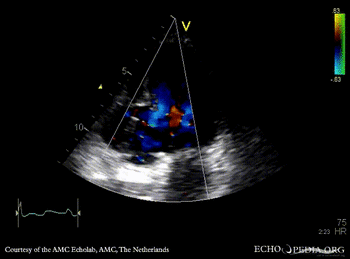

| A2CH: aneurysm of basal inferior wall | A2CH: Color Doppler |